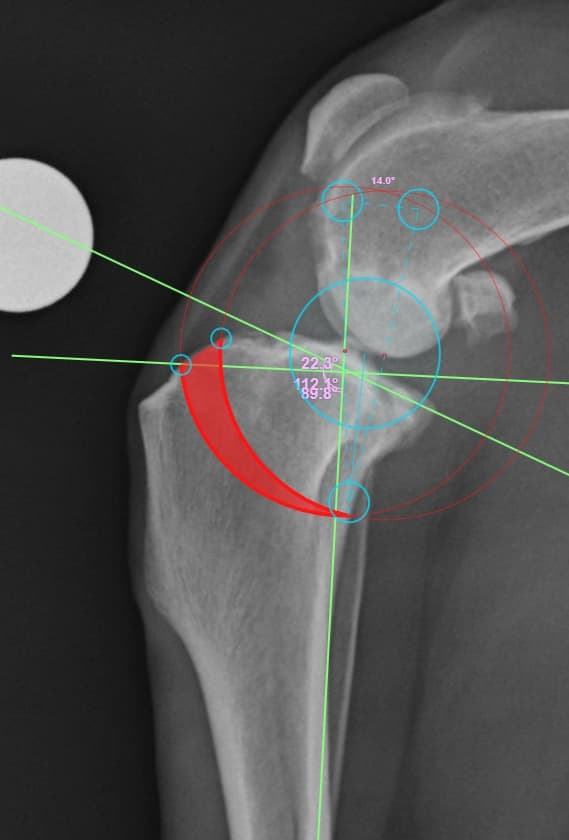

정형외과 전공의 수의사가 직접 수술합니다.

02C-arm을 통해서 좀 더 섬세한 정형외과 수술을 진행하고, 본원에서는 외과적 침습을 최소화 하는 중재적 시술 (기관 협착, 동맥관개존증(PDA), SUB 등)을 진행하고 있습니다.

11유명한 Stryker사 장비. 골절 수술, 절골등 다양한 정형/신경외과 수술시 사용

12정교한 정형외과 도구를 사용하여 신속 정확한 정형외과 수술이 가능

13수술 중 골절 상태 혹은 이식물 적용 후 상태 등 육안으로 명확히 확인하기 힘든 상태를 X-ray 확인하여 정확한 수술 결과를 만들어 내는 것이 가능